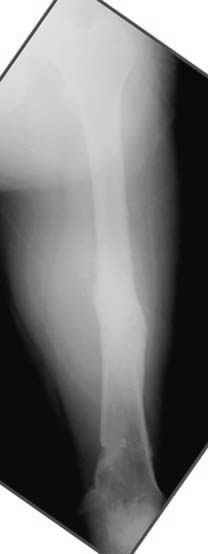

Несколько снимков из моей коллекции, чтобы разьяснить, почему мы до сих пор делаем различные варианты остеотомии.

N3 рисунок окончательный снимок, после операции моя рентгенограмма должен выглядеть примерно как эта картина. На N4 снимке клин перед удалением; N5 послеоперации 3 нед.; N6 окончательная рентгенограмма.

пластическая модель; и коррекция бедра аппаратом Илизарова.